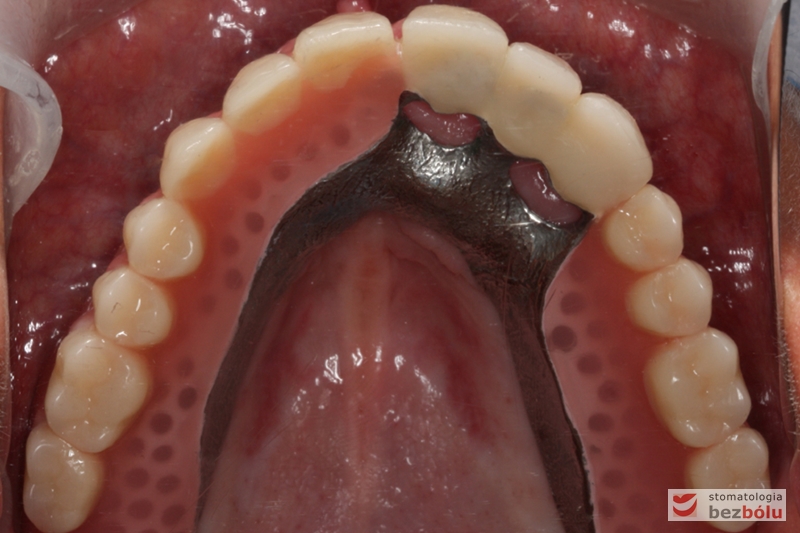

Odbudowa protetyczna szczęki - wykonana z kompozytu w wygodnym kształcie - tzw. "U-shape"

Odbudowa protetyczna szczęki – wykonana z kompozytu w wygodnym kształcie – tzw. „U-shape”